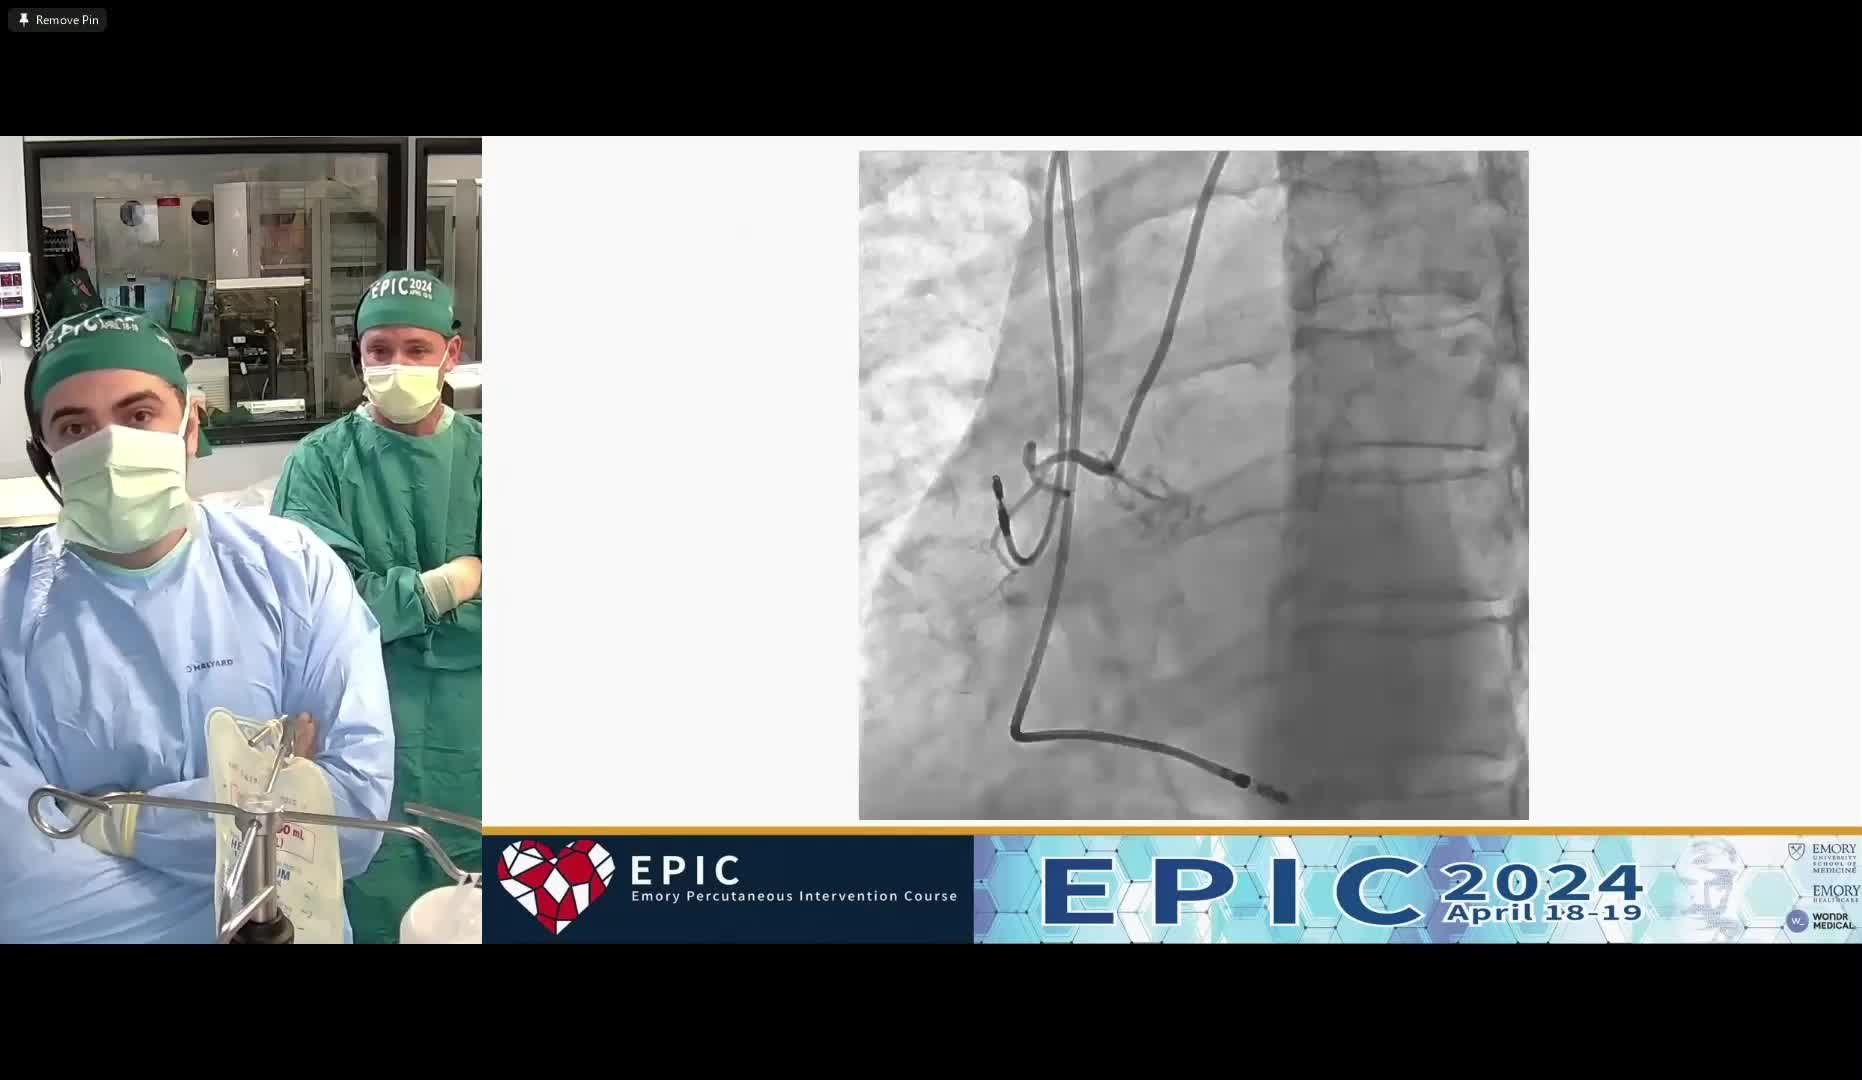

Stentectomy - Endarterectomy for LAD - Full Metal Jacket - with In-Stent Restenosis